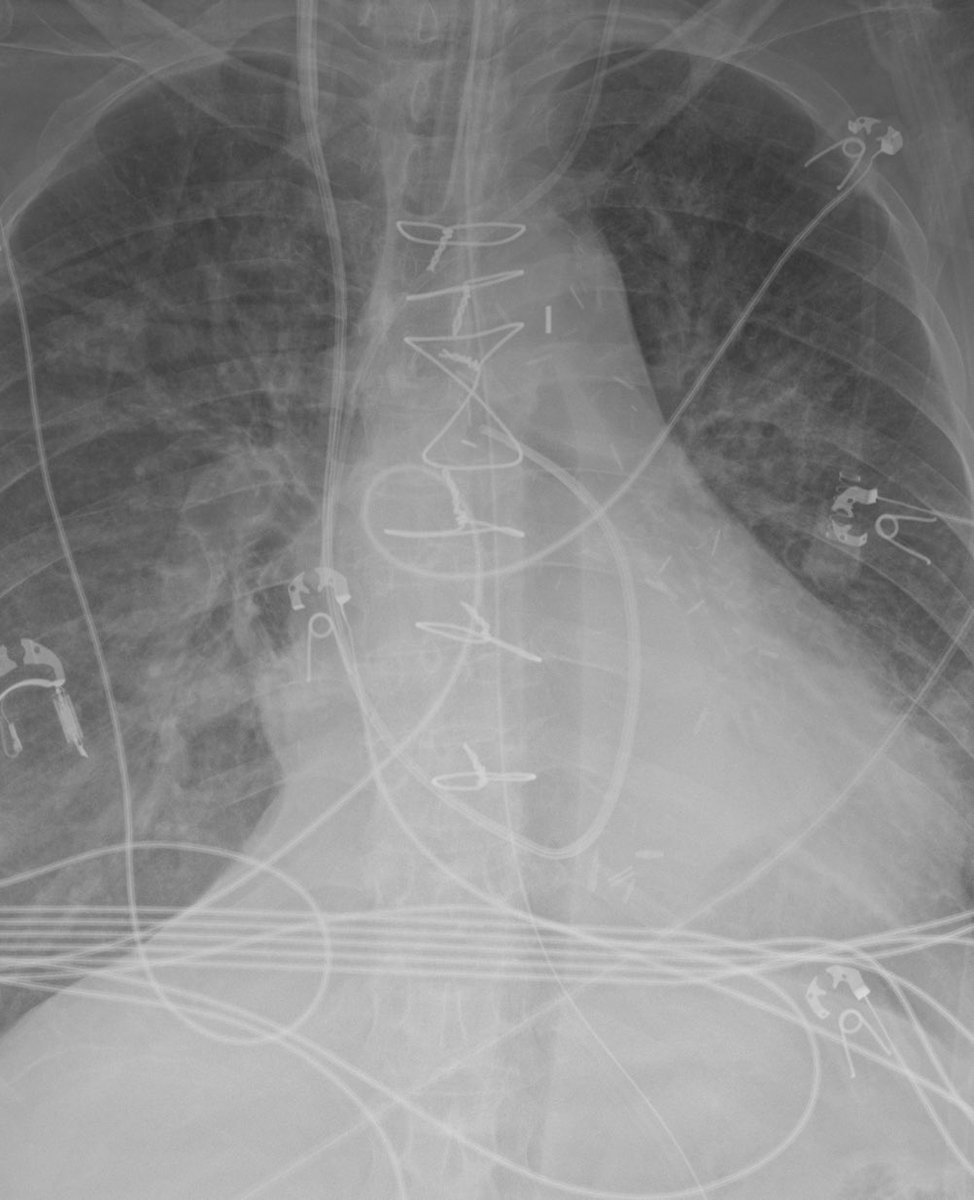

This is a blakemore tube. A sengstaken-blakemore tube. It’s used to tamponade UGI hemorrhage due to varices in emergency situations. Notice the large air bubble that’s been insufflated to tamponade those bleeders

This is a blakemore tube. A sengstaken-blakemore tube.

It’s used to tamponade UGI hemorrhage due to varices in emergency situations.

Notice the large air bubble that’s been insufflated to tamponade those bleeders